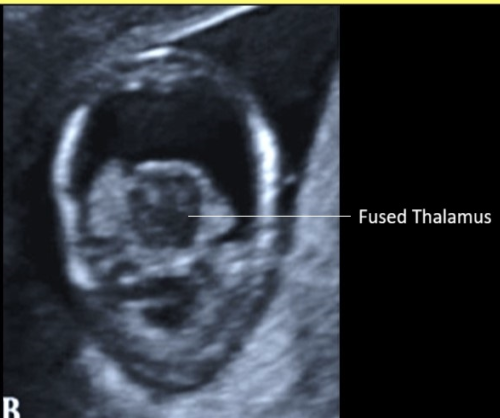

a fused thalamus is identified in which cranial abn

a) semilobar holoprosencephaly only

b) alobar holoprosencephaly only

c) agenesis of corpus callosum + alobar holoprosencephaly

d) alobar + semilobar holoprosencephaly